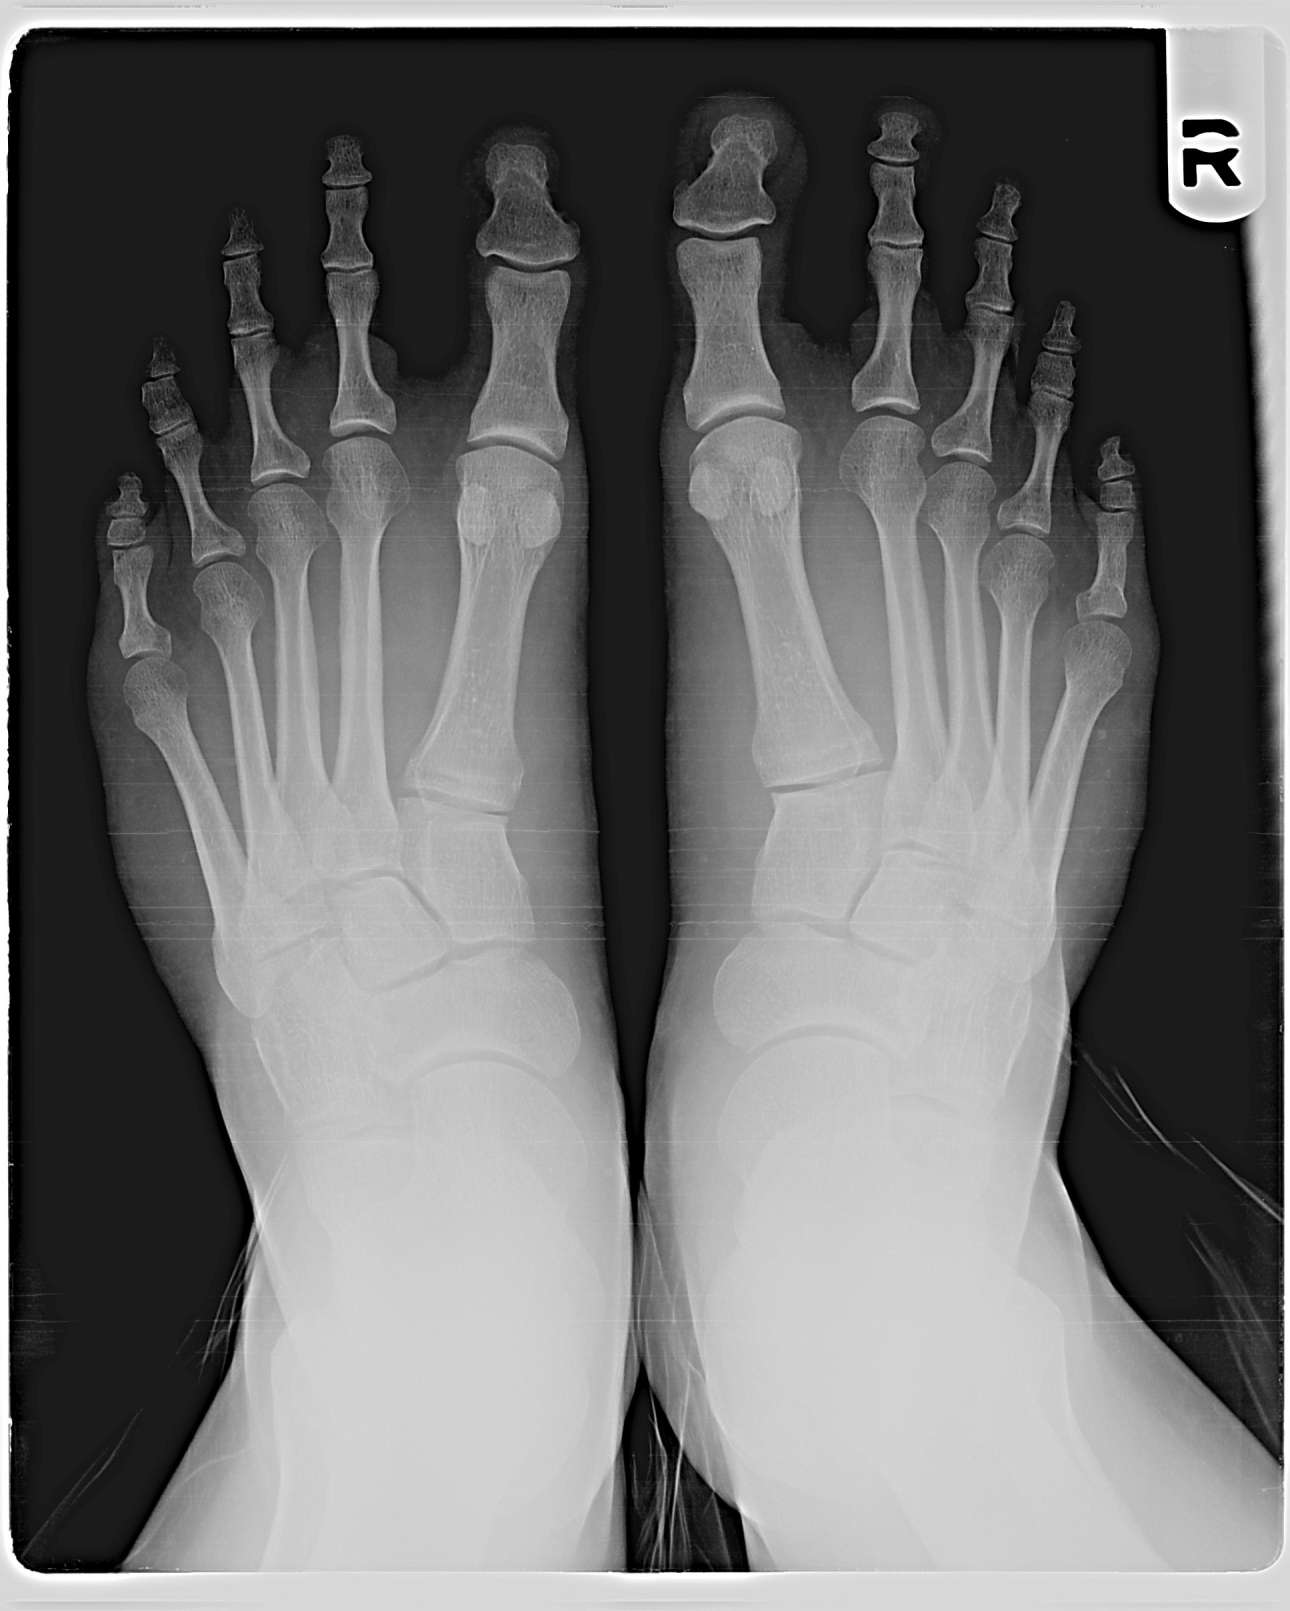

Στις αρχές του 20ου αιώνα, ένας αμερικανός ορθοπεδικός χειρουργός, ο Ντάντλεϊ Μόρτον, ονόμασε το φαινόμενο του δεύτερου μεγαλύτερου δακτύλου, «δάκτυλος του Μόρτον». Ο Μόρτον πίστευε ότι αυτό το δάκτυλο, που το ονόμασε και «Metatarsus atavicus», ήταν ένα αταβιστικό χαρακτηριστικό, που είχε υπάρξει σε πολύ μακρινούς προγόνους, παρόμοιο με την αχρωματοψία, την ανθρώπινη ουρά και την επανεμφάνιση καθολικού τριχώματος.

Το «δάκτυλο του Μόρτον», η ύπαρξη του οποίου δεν συνδέεται κατ’ ανάγκη με την ελληνική καταγωγή, εμφανίζεται στο 15% – 20% των ανθρώπων και μπορεί να προκαλέσει μια σειρά από ορθοπεδικά προβλήματα, όπως η εμφάνιση κάλων ή μια ενόχληση στο μπροστινό μέρος του πέλματος στη βάση του δεύτερου δαχτύλου.

Αν και το όνομά του αναφέρεται στο δεύτερο δάκτυλο του ποδιού, πιο ακριβές θα ήταν να ονομαστεί “πόδι του Μόρτον”, καθώς το πρόβλημα προκαλείται από το πρώτο μετατάρσιο οστό στο πόδι.